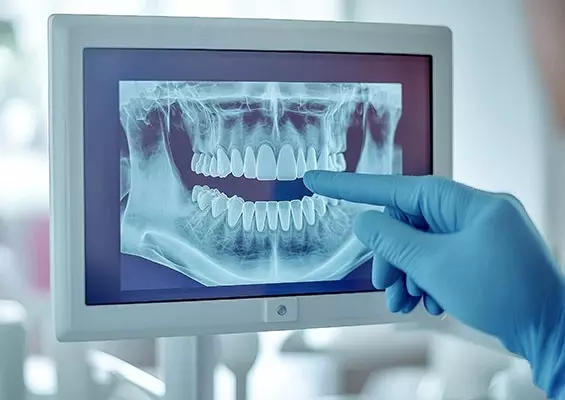

W tym wydaniu m.in: zapalenie przyzębia a ryzyko otępienia, gojenie zmian okołowierzchołkowych, okolica przyszyjkowa jako kompleksowe spojrzenie kliniczne, WawaDent 2024, by-pass złamanego narzędzia.